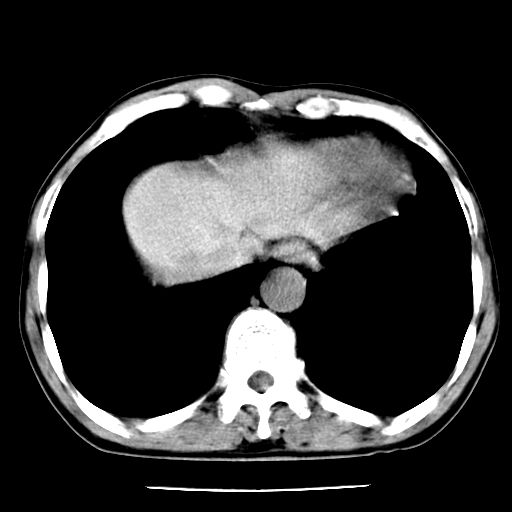

男,59岁,“结核性胸膜炎”30余年,胸部经常疼痛,多次x检查提示“肺部”炎症。腹部疼痛5日,b超提示:“肝内短管结石,余显示不清,建议进一步检查。”

两肺结核并右侧胸腔积液;脾脏、腹腔及腹膜后淋巴结结核[陈旧性];肝内胆管结石

胸部腹部都是结核(双肺。纵隔淋巴结,肝脏,脾脏,肠系膜)

两肺结核并右侧胸腔积液;脾脏、腹腔及腹膜后淋巴结结核[陈旧性];肝内胆管结石。直肠息肉?